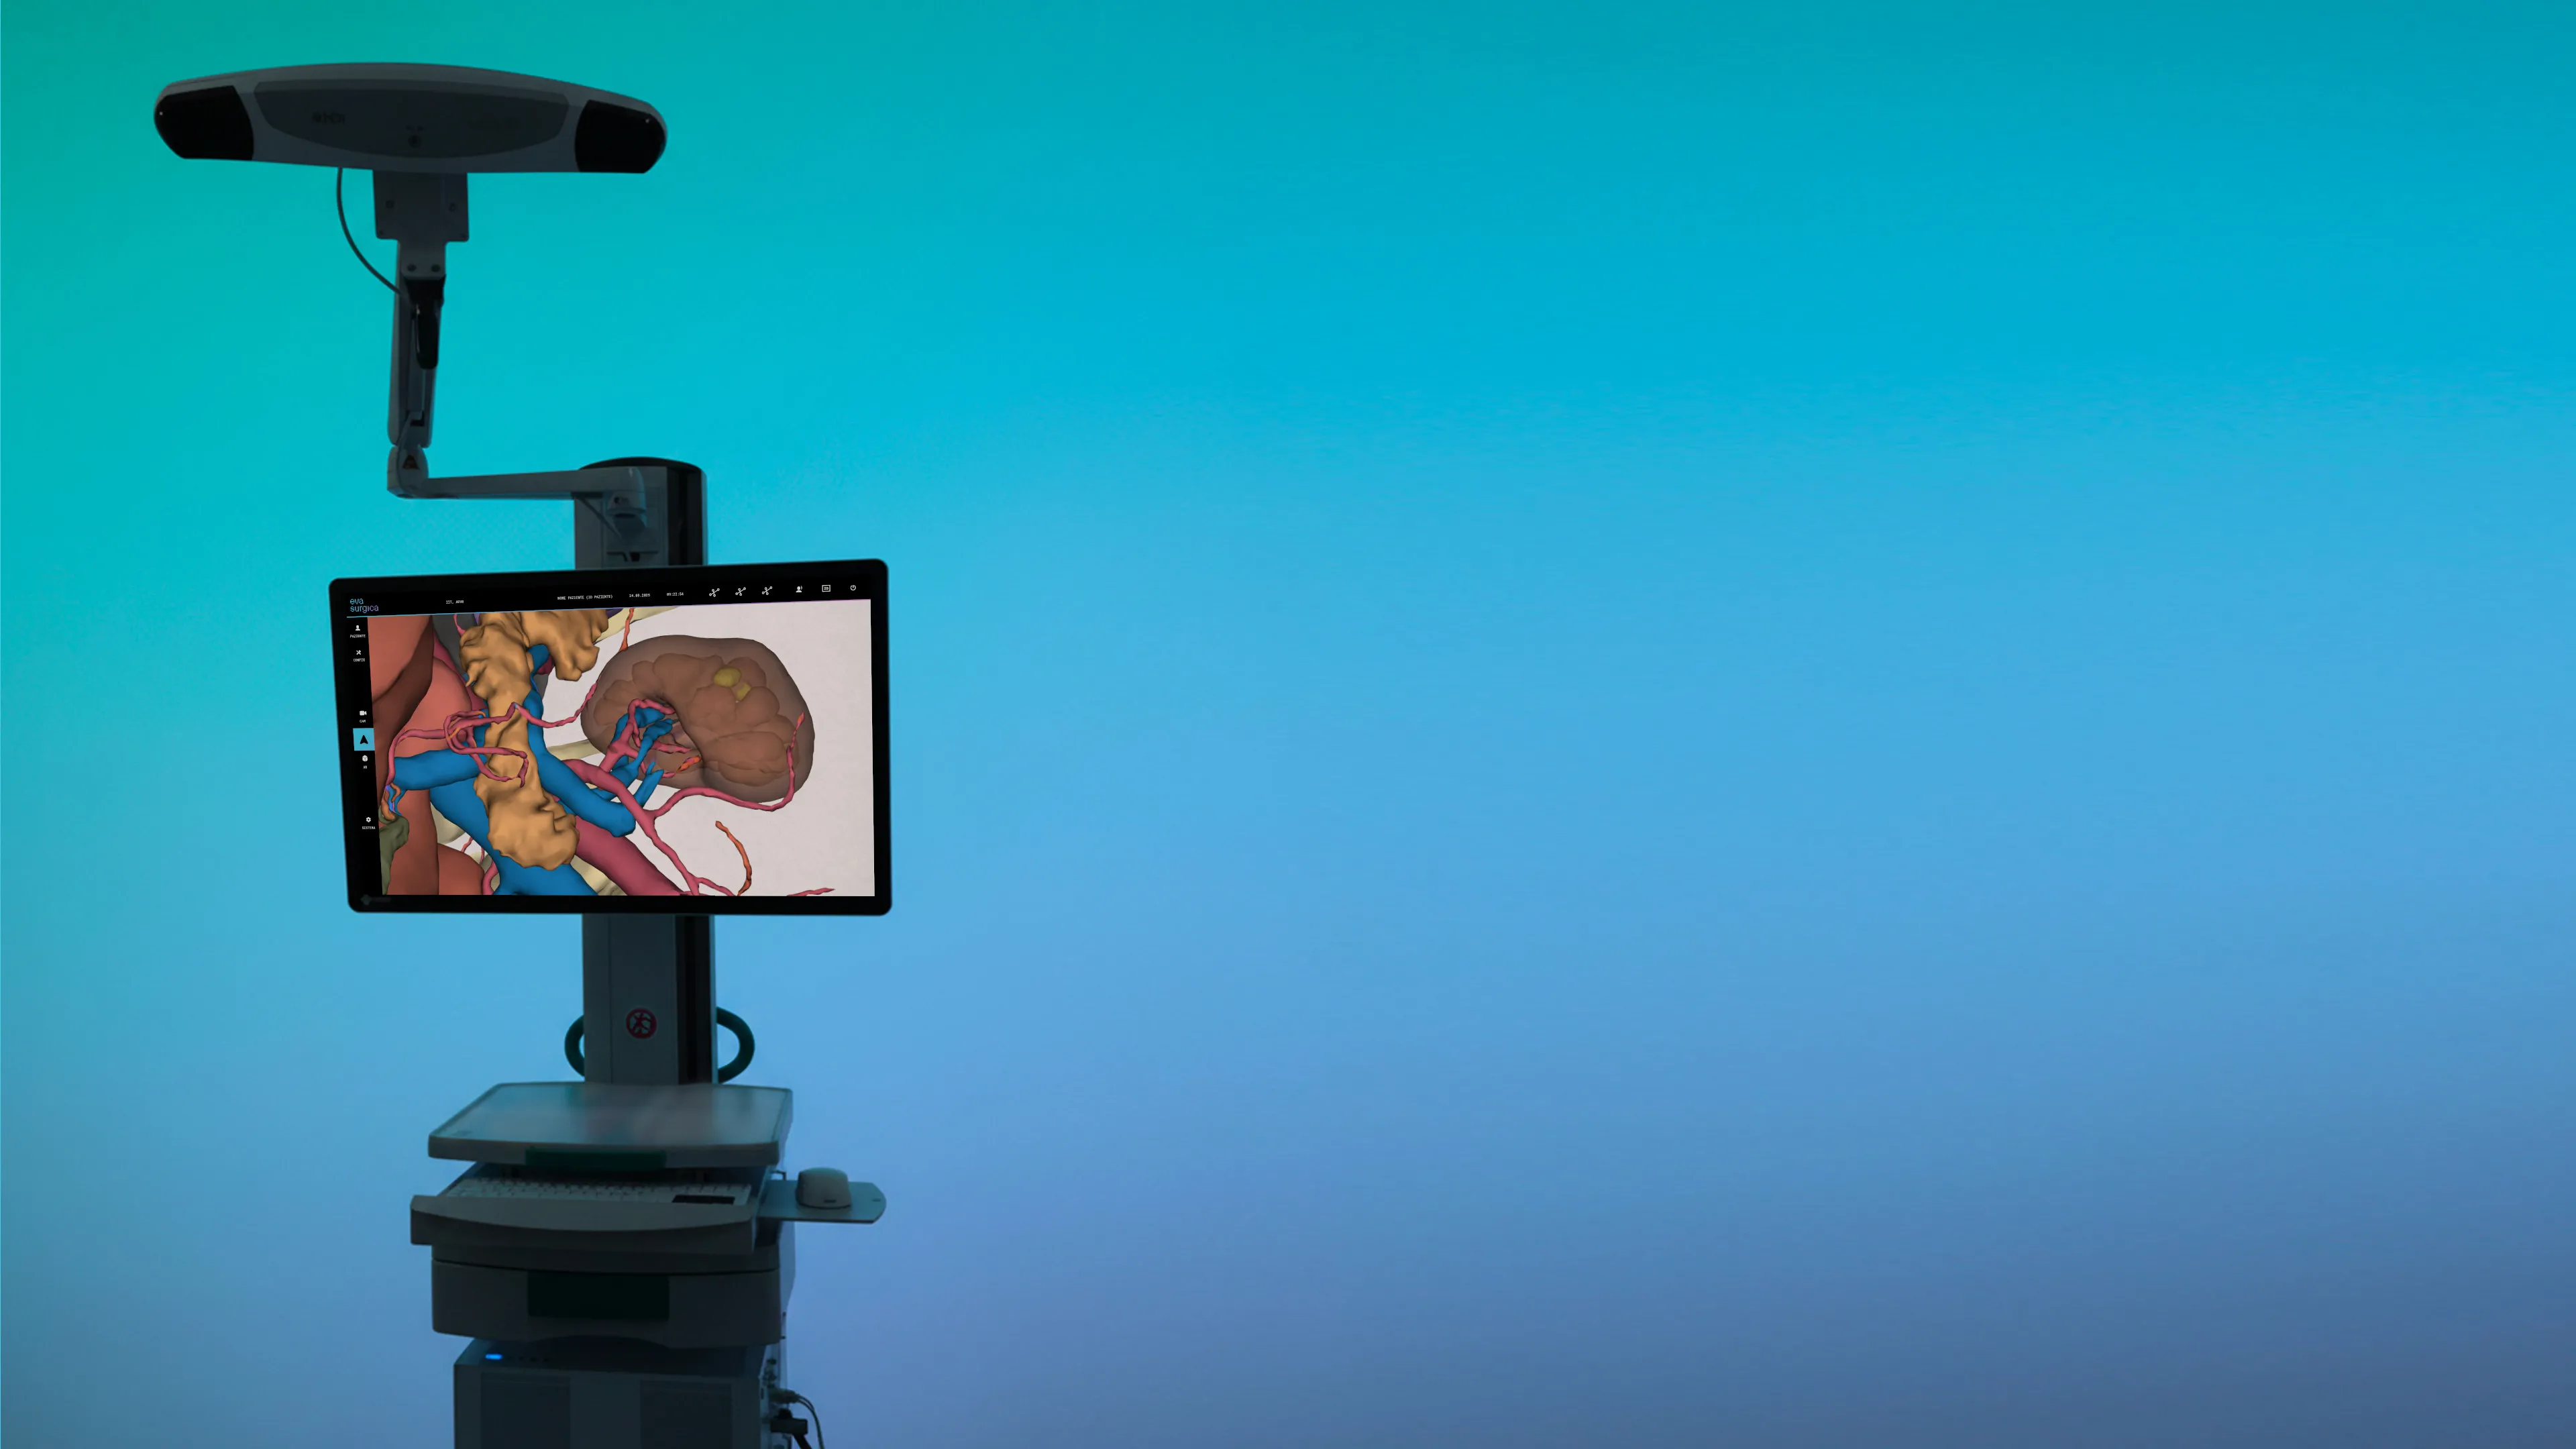

An advanced surgical navigation system that enhances the surgeon’s intraoperative vision with real-time VR/AR representations of the patient’s 3D anatomy, supporting personalized, safer and aware surgery

VIRTUAL REALITY

Anatomy revealed beyond the visible